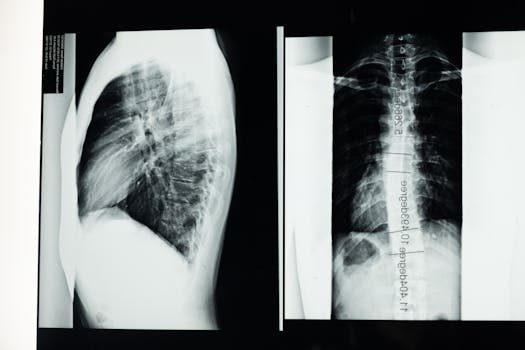

Las curvaturas de la columna vertebral son importantes para su funcionamiento adecuado. La columna no es completamente recta, sino que presenta curvaturas que permiten distribuir el peso de manera uniforme y amortiguar los impactos.

Existen cuatro curvaturas principales: la lordosis cervical y lumbar, y la cifosis torácica y sacra. Estas curvaturas son fundamentales para mantener el equilibrio y la postura del cuerpo humano.

- Escoliosis: una curvatura anormal de la columna que puede desarrollarse en la infancia o adolescencia.